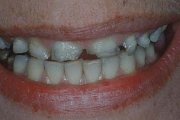

Tetratsükliini liigtarbimise tõttu värvunud hambad